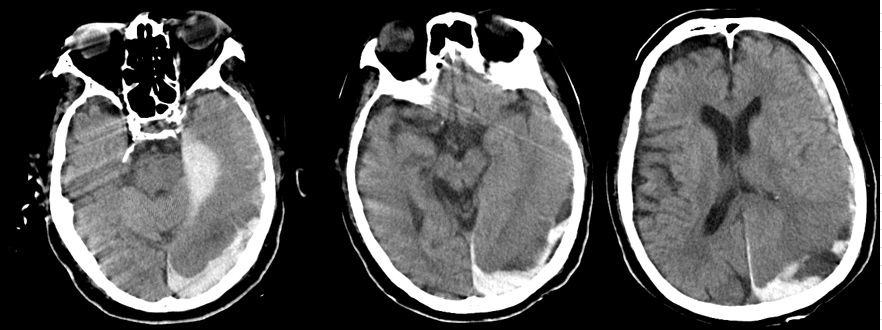

- 9月12日:急性硬膜下血腫

死亡した日の頭部CTで重度の急性硬膜下血腫。医師によれば「その原因はDICによる出血傾向」(頭部打撲の説明なし)。

証拠:頭部CT・急性硬膜下血腫

- 9月12日:出血傾向はごく軽度

PT-INR 1.3, APTT 35 sec, 血小板3.6万/μl, Hb 8.2 g/dl:出血傾向はごく軽度で硬膜下血腫の自然発生は否定的。この時、父は意識がなく自ら動くことはできない状態であったため、頭部を殴打された可能性しか残らない。

この時、撮影された頭部CTで急性硬膜下血腫が認められた。これが父の直接の死因となった。 医師からもその説明があったが、 直接の原因と推定される「頭部打撲」には一切言及がなく(録音記録あり)、 DIC(播種性血管内凝固)に伴う出血傾向による自然出血とのことだった。 しかしほぼ同時に行われた血液検査では、「PT-INR 1.3, APTT 35 sec, 血小板3.6万/μl」と 出血傾向はごく軽度であり、自然発生的に頭蓋内に出血を起こす可能性は皆無と言ってよい。

このことから、直接の死因である急性硬膜下血腫の原因は頭部打撲と確定できる。 この時点で父の意識はなく、自ら動くことは全くできない状態であることから、 頭部打撲は外力によって起こった、と推定される。つまり変死である。